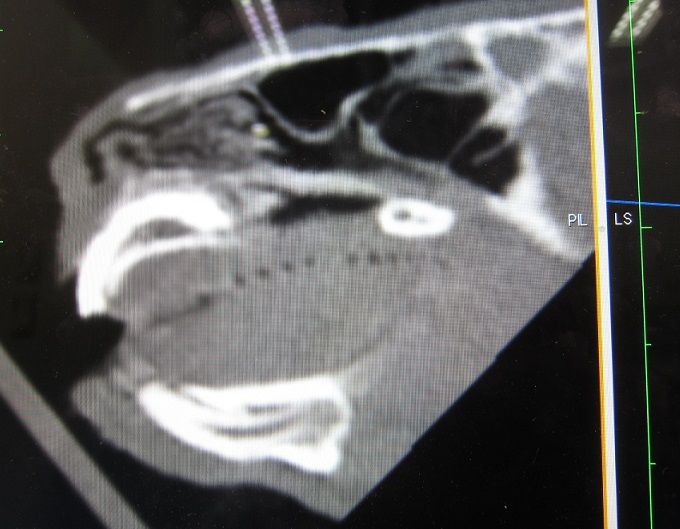

先生が「抱っこしてあげて」と、抱っこすると穴が間近で

露骨に鮮明でエグさ際立ち… 撮影せずにはおれんかった。

(先生に撮ってもらった(^^;))

なんか入りそうで怖いっ!牧草とかささりそうで怖い!